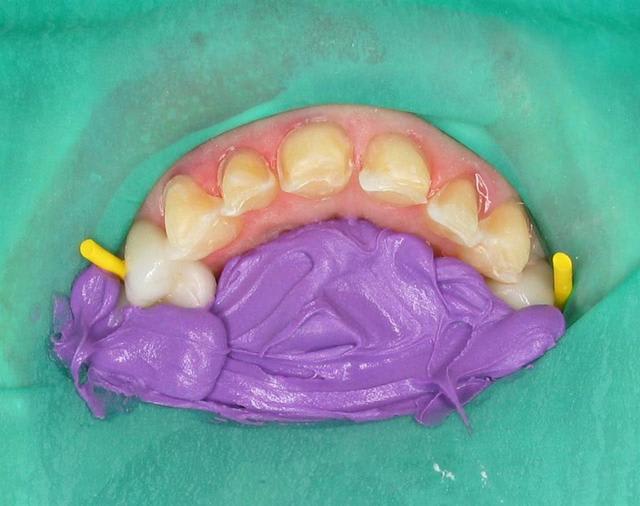

Même et surtout pour les cas complexes (essai et cimentation de 6 à 10 unités céramique)la digue est un outil très utile. Je peux etcher, placer l'adhésif, prendre mon temps pour coller sans avoir la langue, la salive etc.